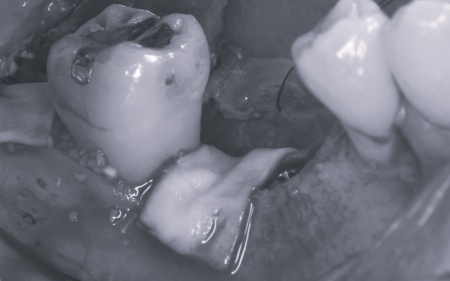

| カウンセリング | 拝見したところ、上下左右の奥歯計8本(第1大臼歯、第2大臼歯)に重度の歯周病が認められました。 歯周病は歯を支えている骨や歯ぐきに炎症が起こる病気です。進行すると歯がぐらついたり、噛む力が弱くなったりします。 さらに悪化すると歯を失う可能性が高くなるだけでなく、周囲の歯にも影響が広がることがあります。 特に下の奥歯2本(左右第1大臼歯)は歯を支えている骨が著しく減少して歯が大きく揺れており、治療して温存することは難しい状態でした。 また、左上の奥歯(第1大臼歯)は過去に詰め物で治療されていましたが、その下で虫歯が再発しています。 以上のことから、下左右の第1大臼歯は抜歯後に歯を補う治療、その他奥歯の治療、再発した虫歯の治療が必要と診断しました。 |

診断結果を踏まえ、まず下左右の第1大臼歯については抜歯したあとにインプラントで補う方法を提案しました。

さらに虫歯が再発していた左上奥歯については、虫歯をしっかりと取り除いたうえで被せ物による修復治療を提案しました。 それぞれのメリット・デメリットを丁寧に説明したところ、治療計画に同意いただきました。 まず、歯周基本治療から開始しました。 下左右の第1大臼歯を抜歯し、その部位にインプラントを埋め込む手術を行いました。同時に、インプラントの隣にある下の第2大臼歯に対して歯周組織再生療法を施しています。 また、左上の奥歯は虫歯を取り除いたあと、歯の形を整えて型取りを行い、最終的にジルコニアクラウンを装着しています。 段階的に治療を進め、すべての治療を終了しました。 |